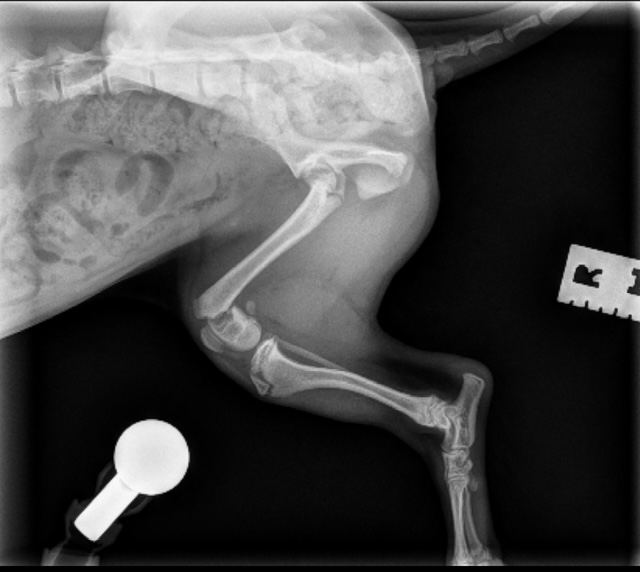

Extracapsular Repair (ExCap)

This procedure stabilizes the knee by placing a strong supportive material outside the joint to limit abnormal movement caused by a torn cranial cruciate ligament. The goal is to restore joint stability, reduce pain, and allow the surrounding tissues to heal and strengthen over time.

Extracapsular (ExCap) Repair #1

Extracapsular (ExCap) Repair #2